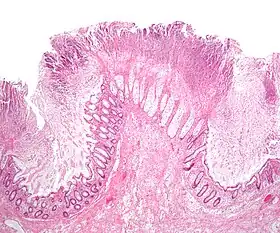

| A micrograph demonstrating cryptitis, a microscopic correlate of colitis. H&E stain. | |

An important investigation in the assessment of colitis is biopsy for histopathology. A very small piece of tissue (usually about 2mm) is removed from the bowel mucosa during endoscopy and examined under the microscope by a histopathologist. A biopsy report generally does not state the diagnosis, but should state any presence of chronic colitis, give an indication of disease activity, as well as state the presence of any epithelial damage (erosions and ulcerations).[4]

Histopathology findings generally associated with chronic colitis include:[4]

Crypt degeneration

Crypt branching and other architectural distortions

Paneth cell (pictured) or gastric metaplasia (only applies in the left colon and rectum)

Other findings include basal plasmacytosis and mucin depletion.[4] Histopathology findings generally associated with active colitis include:[4]

Neutrophilic cryptitis (neutrophils within crypt epithelium)

Crypt abscesses (luminal neutrophilic aggregates)

Gland destruction

Ulceration (seen here as absence of epithelium, and granulation tissue with many fibroblasts)